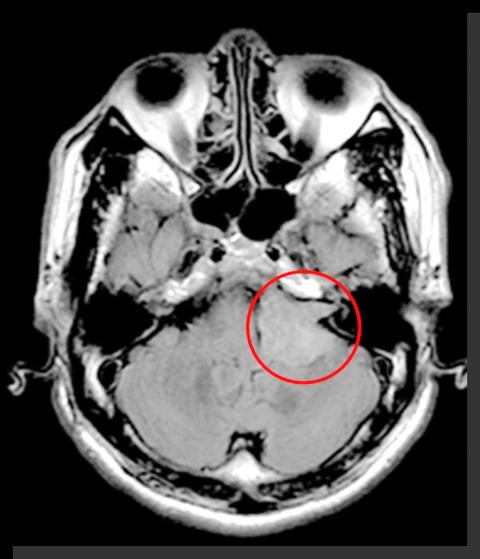

Chuang Hau-yu, head of neurosurgery at the hospital, says that Lai was completely comatose when she arrived at the hospital. A nuclear magnetic resonance (NMR) scan determined that the coma was caused by a brain tumor more than 5cm in diameter located in her left thalamus, which was putting pressure on her brainstem. The hospital immediately arranged for surgery, which was successful.